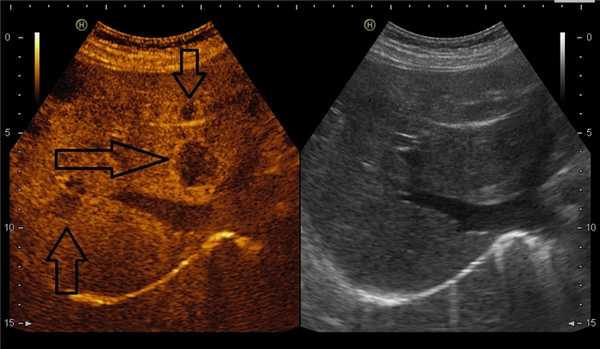

На снимках наглядно видно отличие от обычного УЗИ:

В режиме эхоконтрастирования (слева) четко видны метастазы в печени.